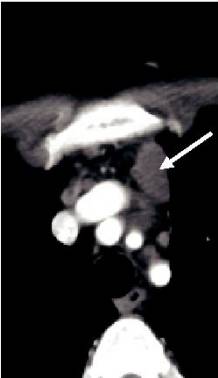

治疗1个月奇迹出现了,CT显示M女士纵隔淋巴结肿大缩小,没有新的肝或纵隔病变(图1A和B和2A和B与图1C和2C),并且在3个月时的影像学检查显示出纵隔淋巴结肿大和肝脏局部病变进一步缓解(图1D和2D)。8个月的影像显示纵隔淋巴结持续缩小,肝脏病变完全消退(图1E和2E)。患者目前仍继续进行治疗。

图2:ABCDE